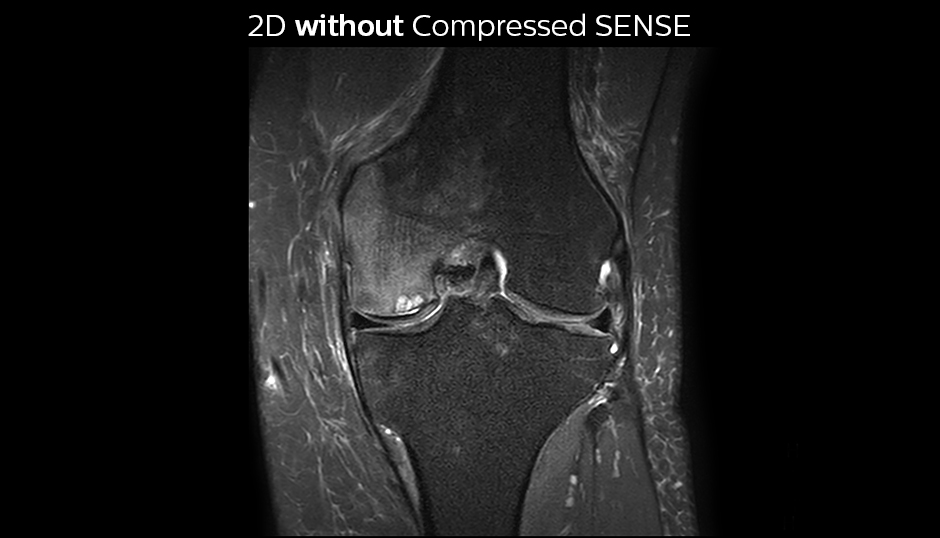

The KSW team also started implementing Compressed SENSE in ankle, elbow, knee and wrist MRI exams, for replacing the 2D PD fat sat with 3D PD fat sat. So far, results look good: it’s possible to obtain a good acquisition time with a high resolution.

A good acquisition time with high resolution is obtained when moving from three 2D acquisitions in three planes to one 3D acquisition with Compressed SENSE. In this example, Compressed SENSE with 3D VIEW PD SPAIR is 50% faster than three separate 2D scans and has improved spatial resolution.

Without Compressed SENSE Scan time 2:55 + 3:37 + 3:51 = 10:23 min. Voxel size 0.55 x 0.65 x 3 mm

Three separate 2D PD scans in three orientations

With Compressed SENSE factor 10 Scan time 5:03 min. Voxel size 0.6 x 0.6 x 0.6 mm

3D VIEW PD SPAIR high resolution knee